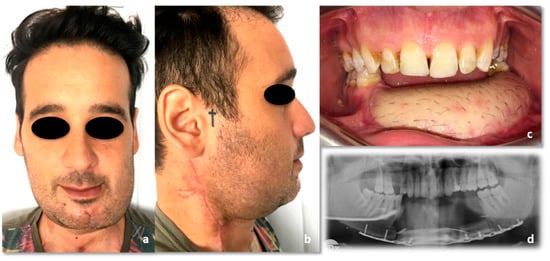

The clinical examination did not highlight any comorbidity. The physical examination showed a mild swelling of the left anterior mandible (Figure 3); there were no palpable lymphadenopathies. No mucosal ulceration in the inferior oral vestibule, neither oral fistula was detectable; no purulent discharge (Figure 4a) occurred after the last antibiotic therapy. The patient was a smoker (3.6 pack/year) and stopped his smoking habit 1 year before the hospitalization. He drank beer occasionally.

Figure 3.

Preoperative pictures. (a) Frontal view; (b) side view.

Figure 4.

(a) Intraoral preoperative picture. The fistula was not noticeable after antibiotic therapy. No ulceration of the oral mucosa was detectable; (b) Orthopantomography following the diagnostic biopsy and lower canine extraction.

Figure 11.

Forty-five-days post-operative condition. (a) Frontal view; (b) side view; (c) intraoral picture; (d) Rx orthopantomography.